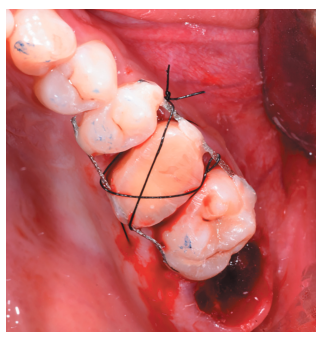

Tras rebajar la oclusión, se dio un punto en cruz con sutura monofilamento (Aragó®, Barcelona, España) alrededor del diente trasplantado para aumentar su fijación (Figura 13), realizándose una radiografía periapical intraoperatoria con técnica de paralelismo (Figura 14).